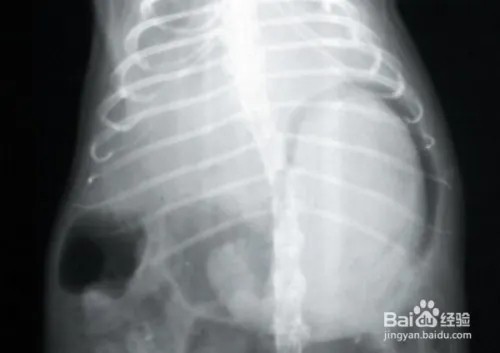

*图为兔兔毛球堵塞

毛球症的主要症状包括便秘、粪便变小变硬、甚至停止排便。严重的肠道堵塞还可能引起肠扭转或肠破裂等严重的并发症,对兔子来说极其危险,甚至会危及生命。